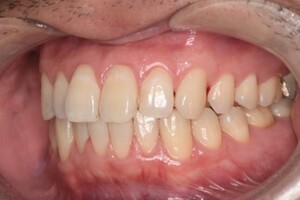

CASE 2

Before

After

基本情報

| 年齢・性別 | 30代・男性 |

| 主訴 | 歯石を取りたい |

| 治療内容 | 超音波スケーラーでの歯石除去 |

| 治療期間 | 60分 |

| 治療費 | 初診料を含め約4,500円 |

| リスク・副作用 | 歯ぐきに違和感や痛みを覚える場合がある。 1週間程度、歯を磨くといつもより出血することがある。 腫れていた歯ぐきが引き締まることで歯ぐきが下がった様に見える。 歯ぐきが下がることで歯がみしやすくなることがある。 一時的に歯の動揺(ゆれ)が増す場合がある。 |